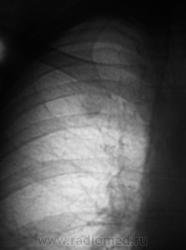

За год "штучка" подросла.

И стала периферическим раком? легкого. Думаю дифф ряд надо начать с этого.

Я тоже сначала подумал о "периферическом", но похоже, "обломался". Сейчас добавлю боковые томограммы.

На томограммах не получили изображение округлой тени. Возможно, она имеет отношение к грудной стенке?

Ничего боелее окостеневшего хряща 1-го ребра справа, как мне кажется...я уже упоминал о его "причудливости" и возможности ошибки...и даже без остеомы или остеохондромы...

А я вижу снижение прозрачности в верхушечном сегменте справа.